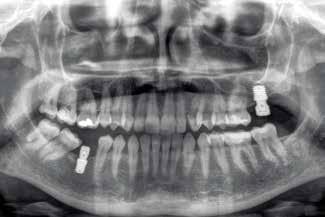

None of the implants failed during the follow-up period, resulting in 100% survival and no adverse surgical or prosthetic events were recorded. Images 1-7 show one of the cases included in the study.

Figure 1. Initial X-ray of the case, where we can see in the second quadrant an edentulous section corresponding to tooth 27 that will be rehabilitated using dental implants.

Figure 2. Planning of the implant to be placed.

Figure 3. Post-surgical panoramic X-ray with the recently placed implant.

Figure 2 Figure 3 Figure 4 Figure 1